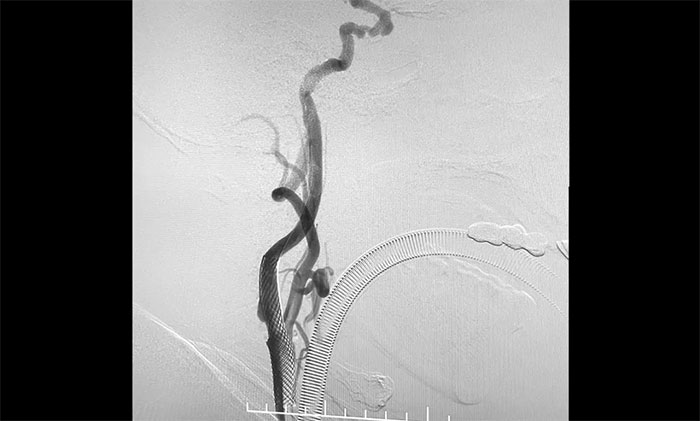

術中,席剛明教授、王貴平博士先對左頸內動脈起始段重度狹窄處進行開通治療,在保護傘下經(jīng)過多次球囊擴張后,順利釋放支架于左頸內動脈起始段至左頸總動脈末段,造影見狹窄明顯改善,順利開通血管。

▲ 頸動脈重度狹窄解除,打通大腦生命線